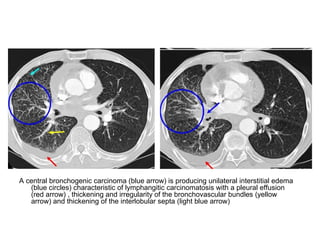

A central bronchogenic carcinoma (blue arrow) is producing unilateral interstitial edema

(blue circles) characteristic of lymphangitic carcinomatosis with a pleural effusion

(red arrow) , thickening and irregularity of the bronchovascular bundles (yellow

arrow) and thickening of the interlobular septa (light blue arrow)